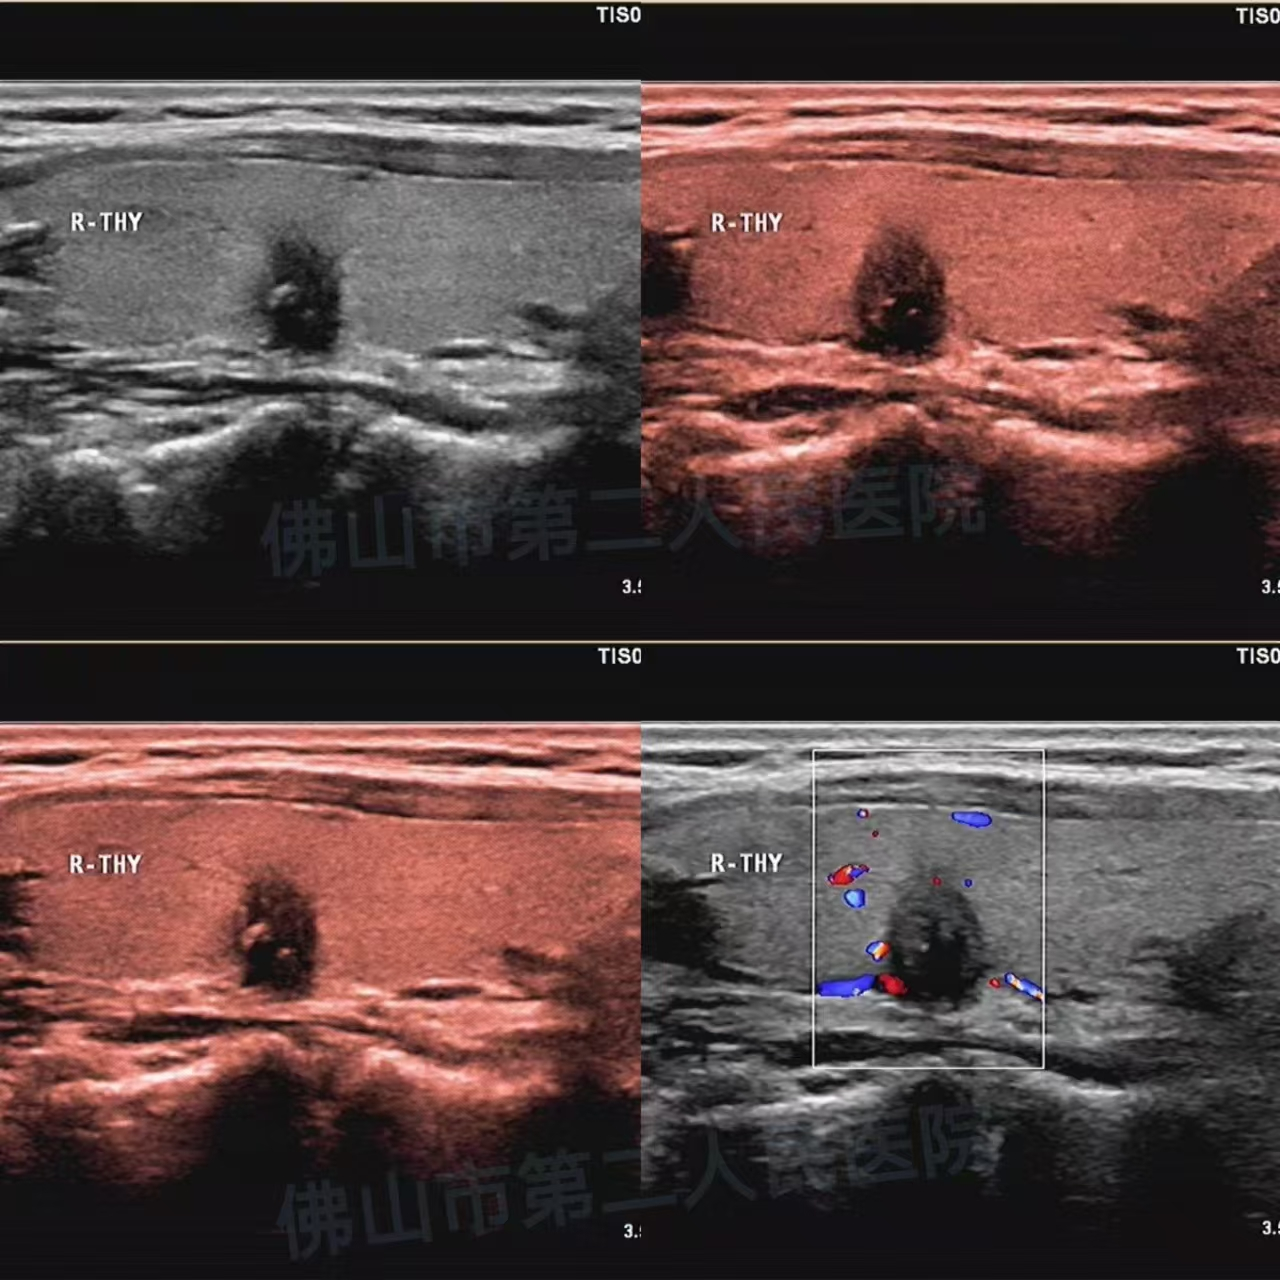

(病例1:恶性结节,实性,低回声,纵横比>1,点状及粗大钙化)